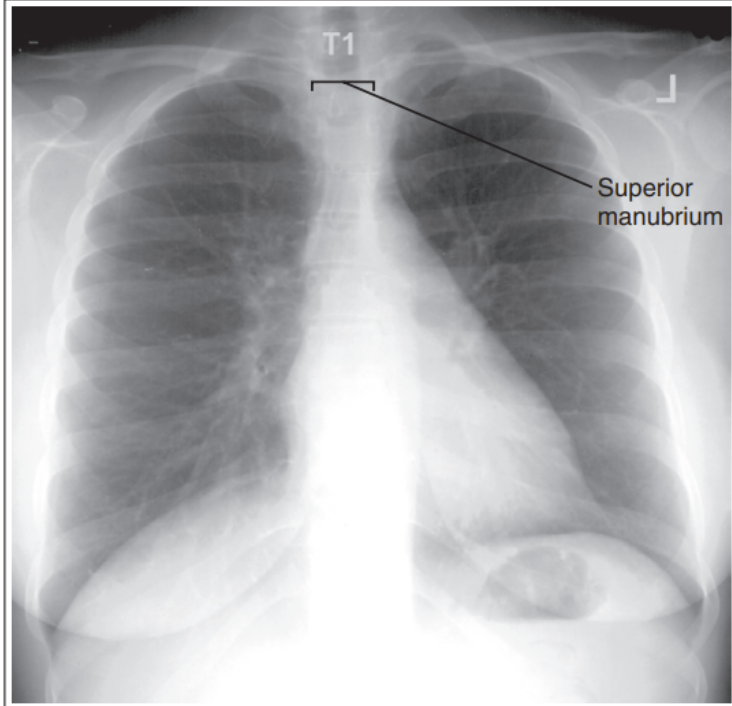

Superior midcoronal tilt posteriorly

More than 2.5cm of apices are demonstrated above clavicle